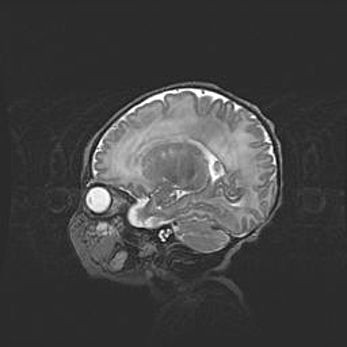

Аномалия Денди-Уокера. Признаки гипоплазии мозолистого тела.

Возраст: 5 месяцев 3 дня

Вес: 5550 г

Пол: мужской

Окружность головы: 39 см

Срок гестации: 40 недель

Аномалия Денди-Уокера – это порок развития головного мозга, для которого характерна триада симптомов: гипотрофия или аплазия червя мозжечка и/или полушарий мозжечка, расширение четвёртого желудочка с формированием ликворной кисты задней черепной ямки, гипертензионная гидроцефалия различной степени.

Гипоплазия мозолистого тела относится к дефектам внутриутробного этапа развития мозговой ткани, возникающим в процессе закладки структур головного мозга, что происходит на начальных этапах развития эмбриона.